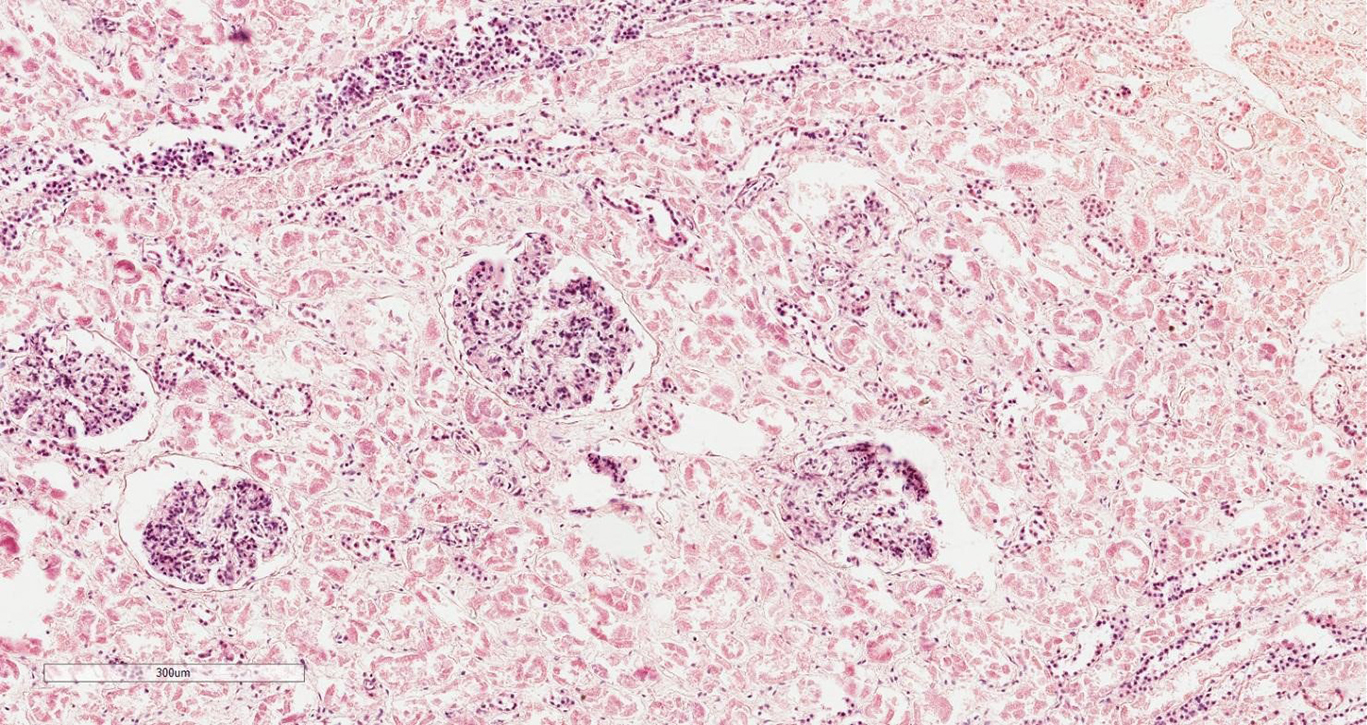

Преэклампсия поражает почки как функционально, так и морфологически. Почечная гемодинамика снижается, а экскреция белка с мочой увеличивается, частично из-за поражений клубочков, где сочетание изменений даёт характерные проявления и позволяет дифференцировать преэклампсическую нефропатию от других гломерулярных изменений, связанных с артериальной гипертензией во время беременности. В процессе преэклампсии клубочки диффузно увеличены и бескровны, что обусловлено не пролиферацией, а гипертрофией внутрикапиллярных клеток. Эти изменения, лучше всего описываемые ультраструктурно, включают гипертрофию цитоплазматических органелл в эндотелиальных и иногда — мезангиальных клетках, особенно лизосомах, которые претерпевают заметное увеличение и вакуолизацию (из-за накопления свободных нейтральных липидов). Эти реактивные изменения получили название «гломерулярный капиллярный эндотелиоз». Другие поражения, наблюдаемые время от времени, включают субэндотелиальные и мезангиальные электронно-плотные отложения, а также интерпозицию цитоплазмы мезангиальных клеток или мезангиального матрикса вдоль нормальной в остальном базальной мембраны. Наконец, почечные поражения считаются полностью обратимыми, и заболевание не оказывает отдалённого кардиоренального влияния на своих пациентов.

Гистологическая картина характеризуется набуханием и отслойкой клубочковых эндотелиоцитов, субэндотелиальными отложениями фибриноида, закупоркой клубочковых капилляров, снижением плотности и размера эндотелиальных отверстий и утолщением клубочковой базальной мембраны. Эти изменения, типичные для тромботической микроангиопатии, ухудшают гидравлическую проницаемость капилляров клубочков и уменьшают площадь поверхности фильтрации, что приводит к снижению скорости клубочковой фильтрации [32, 33].